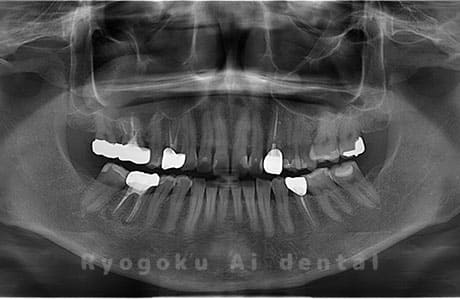

Case03

- 上顎、下顎の親知らず

- 上下4本の親知らずを抜歯したケースです。

<リスク・副作用>

手術後は痛み、腫れ、痺れなどの副作用が生じる場合があります。